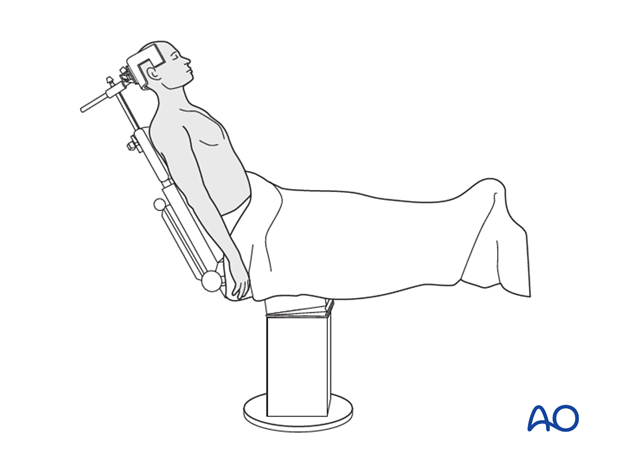

Patient Preparation & Positioning

The optimal patient position for GT fracture fixation is the beach chair position, offering numerous advantages for exposure and manipulation.

* Beach Chair Position:

* The patient is positioned semi-recumbent (30-70 degrees of trunk elevation).

* The head is secured in a headrest, ensuring the neck is neutral and venous drainage is uncompromised.

* The involved arm is draped free, allowing full manipulation (abduction, adduction, internal, and external rotation) to facilitate reduction maneuvers and confirm range of motion post-fixation.

* Padding is placed under pressure points (heels, sacrum, contralateral elbow).

* A beanbag can be used to stabilize the torso.

* This position allows for simultaneous access to the anterior and posterior aspects of the shoulder, should it be required, and facilitates fluoroscopic imaging.

This illustration depicts a patient positioned in the beach chair configuration, which is standard for most shoulder procedures, including fixation of greater tuberosity fractures.

* Fluoroscopy Setup:

* The C-arm fluoroscopy unit must be positioned to allow unobstructed AP, lateral (true scapular Y), and axillary views of the shoulder. It is critical to confirm the ability to obtain these views before draping.

* Anesthesia: General anesthesia is typically employed. A regional nerve block (e.g., interscalene block) can be considered pre-operatively for post-operative pain management, but its use during surgery may mask nerve irritation symptoms.

* Sterile Preparation and Draping: The shoulder and entire upper extremity, including the hand, are prepped and draped in a sterile fashion, allowing for full range of motion during the procedure.